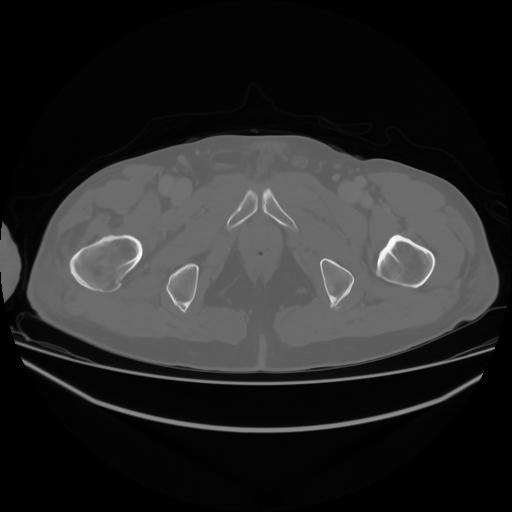

4 CUERPO,CE,Axial,3.0,CUERPO,,